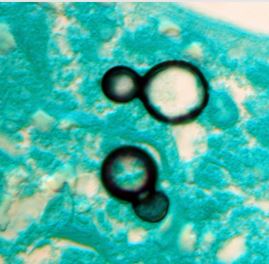

The controlled and efficient release of pharmaceuticals through the use of nanoparticles is regarded as one of the most sophisticated approaches in drug delivery. The fungal membrane is the focus of existing antifungal medications, especially azoles, although resistance to these treatments is growing, necessitating new delivery strategies.

In this study, the ARI team created Nikkomycin-loaded polymeric nanoparticles using the chitin synthesis inhibitor Nikkomycin — which is generated by the bacterial species Streptomyces.

Since human cells lack chitin — a crucial component of fungal cell walls — antifungal medicines can specifically target these cells. It was discovered that the drug-loaded nanoparticles efficiently prevented the growth of Aspergillus species, which in turn prevented the fungal illnesses Aspergillosis, which is caused by Aspergillus fumigatus and Aspergillus flavus.